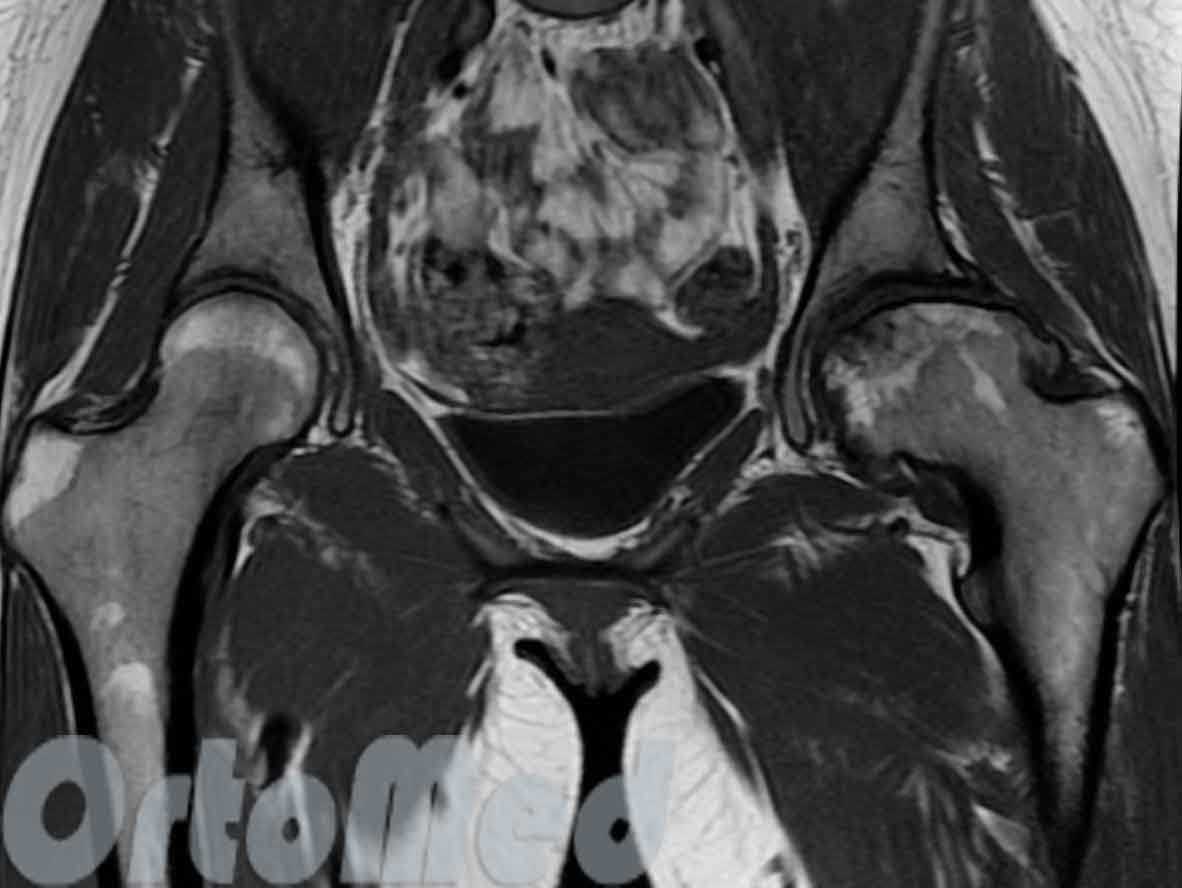

Асептический некроз головки левой бедренной кости

На магнитно-резонансной томографии четко виден очаг разрушения в нагружаемой части головки левой бедренной кости